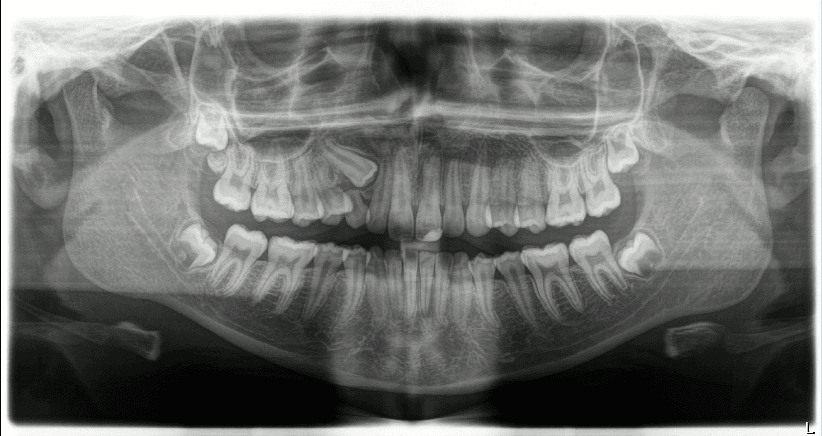

Pacientes infantis na “fase patinho feio”:

A fase do patinho feio é um período natural do desenvolvimento dentário, pode ocorrer dos 7 aos 12 anos de idade, na dentição mista existe a presença de espaços favoráveis para a erupção dos dentes permanentes. O fechamento prematuro desses espaços pode comprometer o processo de erupção e o desenvolvimento ósseo, levando a problemas futuros de oclusão e alinhamento dentário.

Durante essa fase, é essencial monitorar o crescimento e a erupção dos dentes permanentes, evitando intervenções desnecessárias que possam interferir no processo natural.